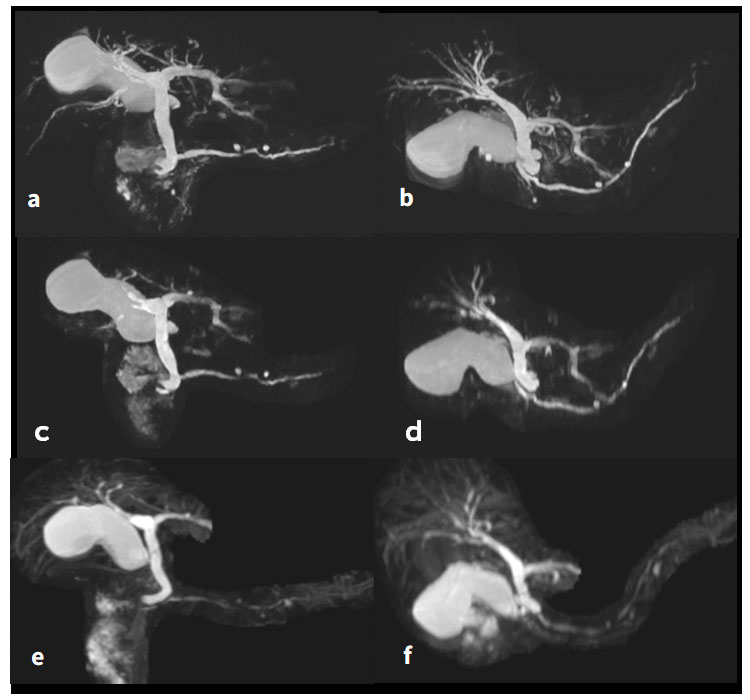

Fig.3-1ab,3-2abがArtist Evo, Fig.3-1c,3-2cが旧装置HDxtで撮像された3D MRCPである. 旧装置ではDWI以外へのFOCUSは対応していなかったため, 折り返りアーチファクトを防止するには, 位相方向はRL一択となり, FOVは横に長く横たわる胆嚢・膵臓を収めるために正方形35cmと大きな値を使用していた. マトリクス数を増やせば, 呼吸同期も相まって撮像時間の大幅な延長を来たすため, pixel sizeを小さくすることは容易でなかった (Fig.3-1c,3-2c). FOCUSはFOV外に強力なサチュレーションパルスを施すことで, 折り返りアーチファクトのないsmall FOVを実現する技術である. これを使用することで,折り返りアーチファクトに臆せず, 位相方向をSIに設定できる. DLによるSNR向上を前提にFOVを小さくでき, phase FOVを絞り横に長い長方形FOVとすることで, 胆嚢・膵臓をImagingするマトリクス数が相乗的に増加する. 結果, pixel sizeが大幅に小さくなり, Fig.3-1ab,3-2abの様な画質改善が可能となった. (a)は呼吸同期法, (b)は息止め法による画像である. 息止め法の場合はデータ収集時間に制約があるため, マトリクス数をあまり増やせず, 膵管描出不良を避けるため, HyperSENSE(Compressed Sensing;CS)は使用していない. そのため, FOCUSにて位相FOVを絞ることで, データ量を少なくし, 分解能を向上しながらも, 息止め時間の短縮に寄与している. 呼吸同期法においては, データ収集時間の制約は息止め法ほど厳しくなく, マトリクス数を増やすことが可能となるため, HyperSENSEを使用することで撮像時間短縮を図っている. また, 旧装置では, 肝内胆管や他臓器に起因するノイズが多かったが, Artist Evo ではDLによって各種ノイズが軽減され, MIP作成における胆管・膵管の切り出し作業も大幅に簡素化・時間短縮化を図ることができている.

Artist_Yokohamaminamikyousai04.jpg

Fig.3 同一被験者における3D MRCPのArtist Evo(呼吸同期法・息止め法)と、HDxt(呼吸同期法)の比較

(a) Artist Evo, 呼吸同期, w/DL + CS + Focus (Coronal View)

(b) Artist Evo, 呼吸同期 w/DL + CS + Focus (Top-Down View) Pixel size : 0.86*0.65*1.5 (0.75), pFOV0.7

(c) Artist Evo, 息止め, w/DL + Focus (Coronal View)

(d) Artist Evo, 息止め, w/DL + Focus (Top-Down View) Pixel size : 0.97*0.73*2.8 (1.4) , pFOV0.5

(e) HDxt, 呼吸同期, w/o DL (Coronal View)

(f) HDxt, 呼吸同期, w/o DL(Top-Down View) Pixel size : 1.09*1.56*2.2 (1.1)